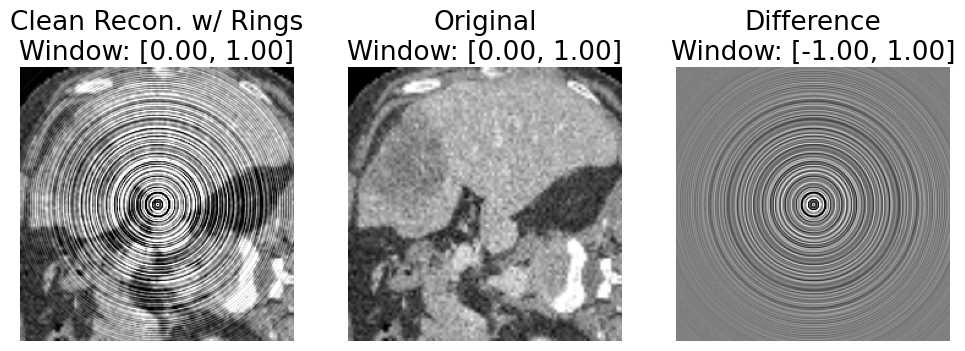

Refer to caption

Figure 4. Result of our proposed approach (first image is OdistortedO_{distorted}). For ease of visualization, we simulate 5 adjacent detector channels with gain error -10%.

Figure 5. Samples from our distorted OrganAMNIST dataset exhibiting our simulated ring artifact with up to 10% gain error in all simulated detectors.

See Fig. 4 for an example following those used in discussion thus far. See Fig. 5 for an example of the actual ring distortion we used in our experiments, which applies up to 10% gain error to all simulated detectors.